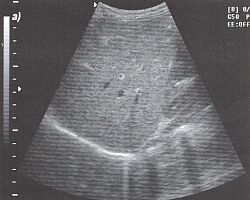

3.Техника получения подреберного среза печени. Помещаем датчик под правый нижний реберный край (рис. 3) и, легко нажимая на кожу, производим веерообразные движения сверху вниз и снаружи кнутри (рис. 4). Когда мы направляем датчик вверх, то видим печеночные вены (рис. 5) и изучаем сегментарное строение печени. Затем, направляя датчик немного вниз, можно увидеть вены воротной системы (рис. 6).

4.Техника получения продольного среза печени. Плотно устанавливаем датчик на кожу под мечевидный отросток и направляем его вверх (рис. 7), затем смещаем в латеральном направлении (параллельно исходной позиции) так, чтобы осмотреть всю печень (рис. 8). Этот срез идеален для исследования левой доли печени.